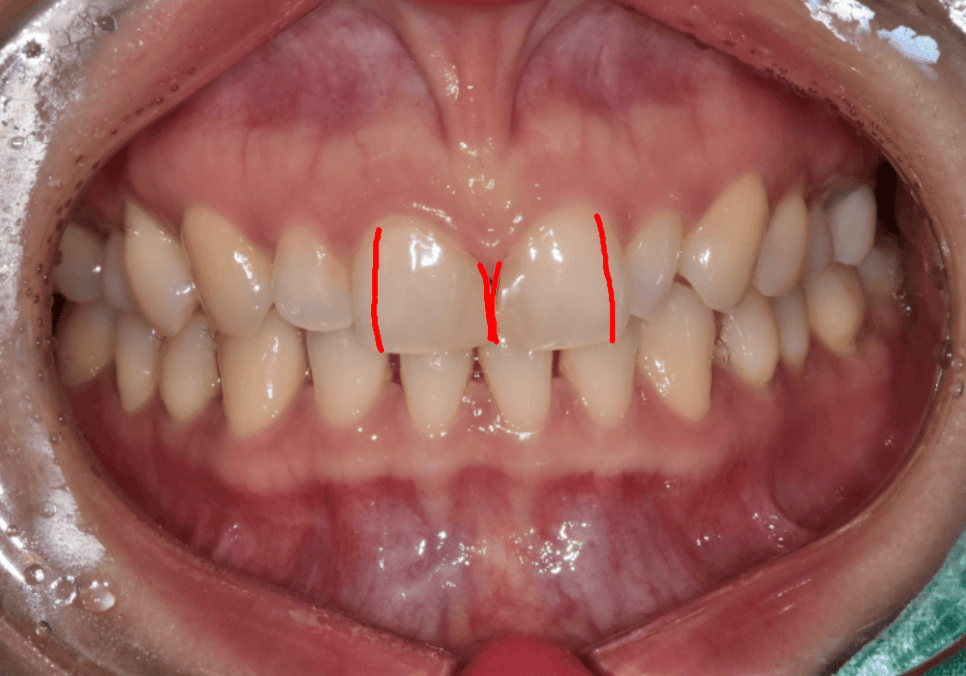

이 상태에서

옆 치아만 키우게 되면

앞니가 답답해 보이거나

전체가 앞으로 튀어나온 듯한

부자연스러운 느낌이 생길 수 있습니다.

그래서 이 환자분은

작은 치아를 키우는 치료가 아니라,

강일동 라미네이트 가격 망설여질 때 꼭 확인해야 할 '이것'

앞니 네 개의 크기를 다시 나누는 치료가

필요한 경우였습니다.

가운데 앞니는

눈에 띄지 않게 크기를 조금 줄이고,

230520

옆 치아는 자연스럽게 키워

앞니 네 개가 비슷한 비율로 보이도록

4개의 라미네이트로 진행해드렸습니다.

230509